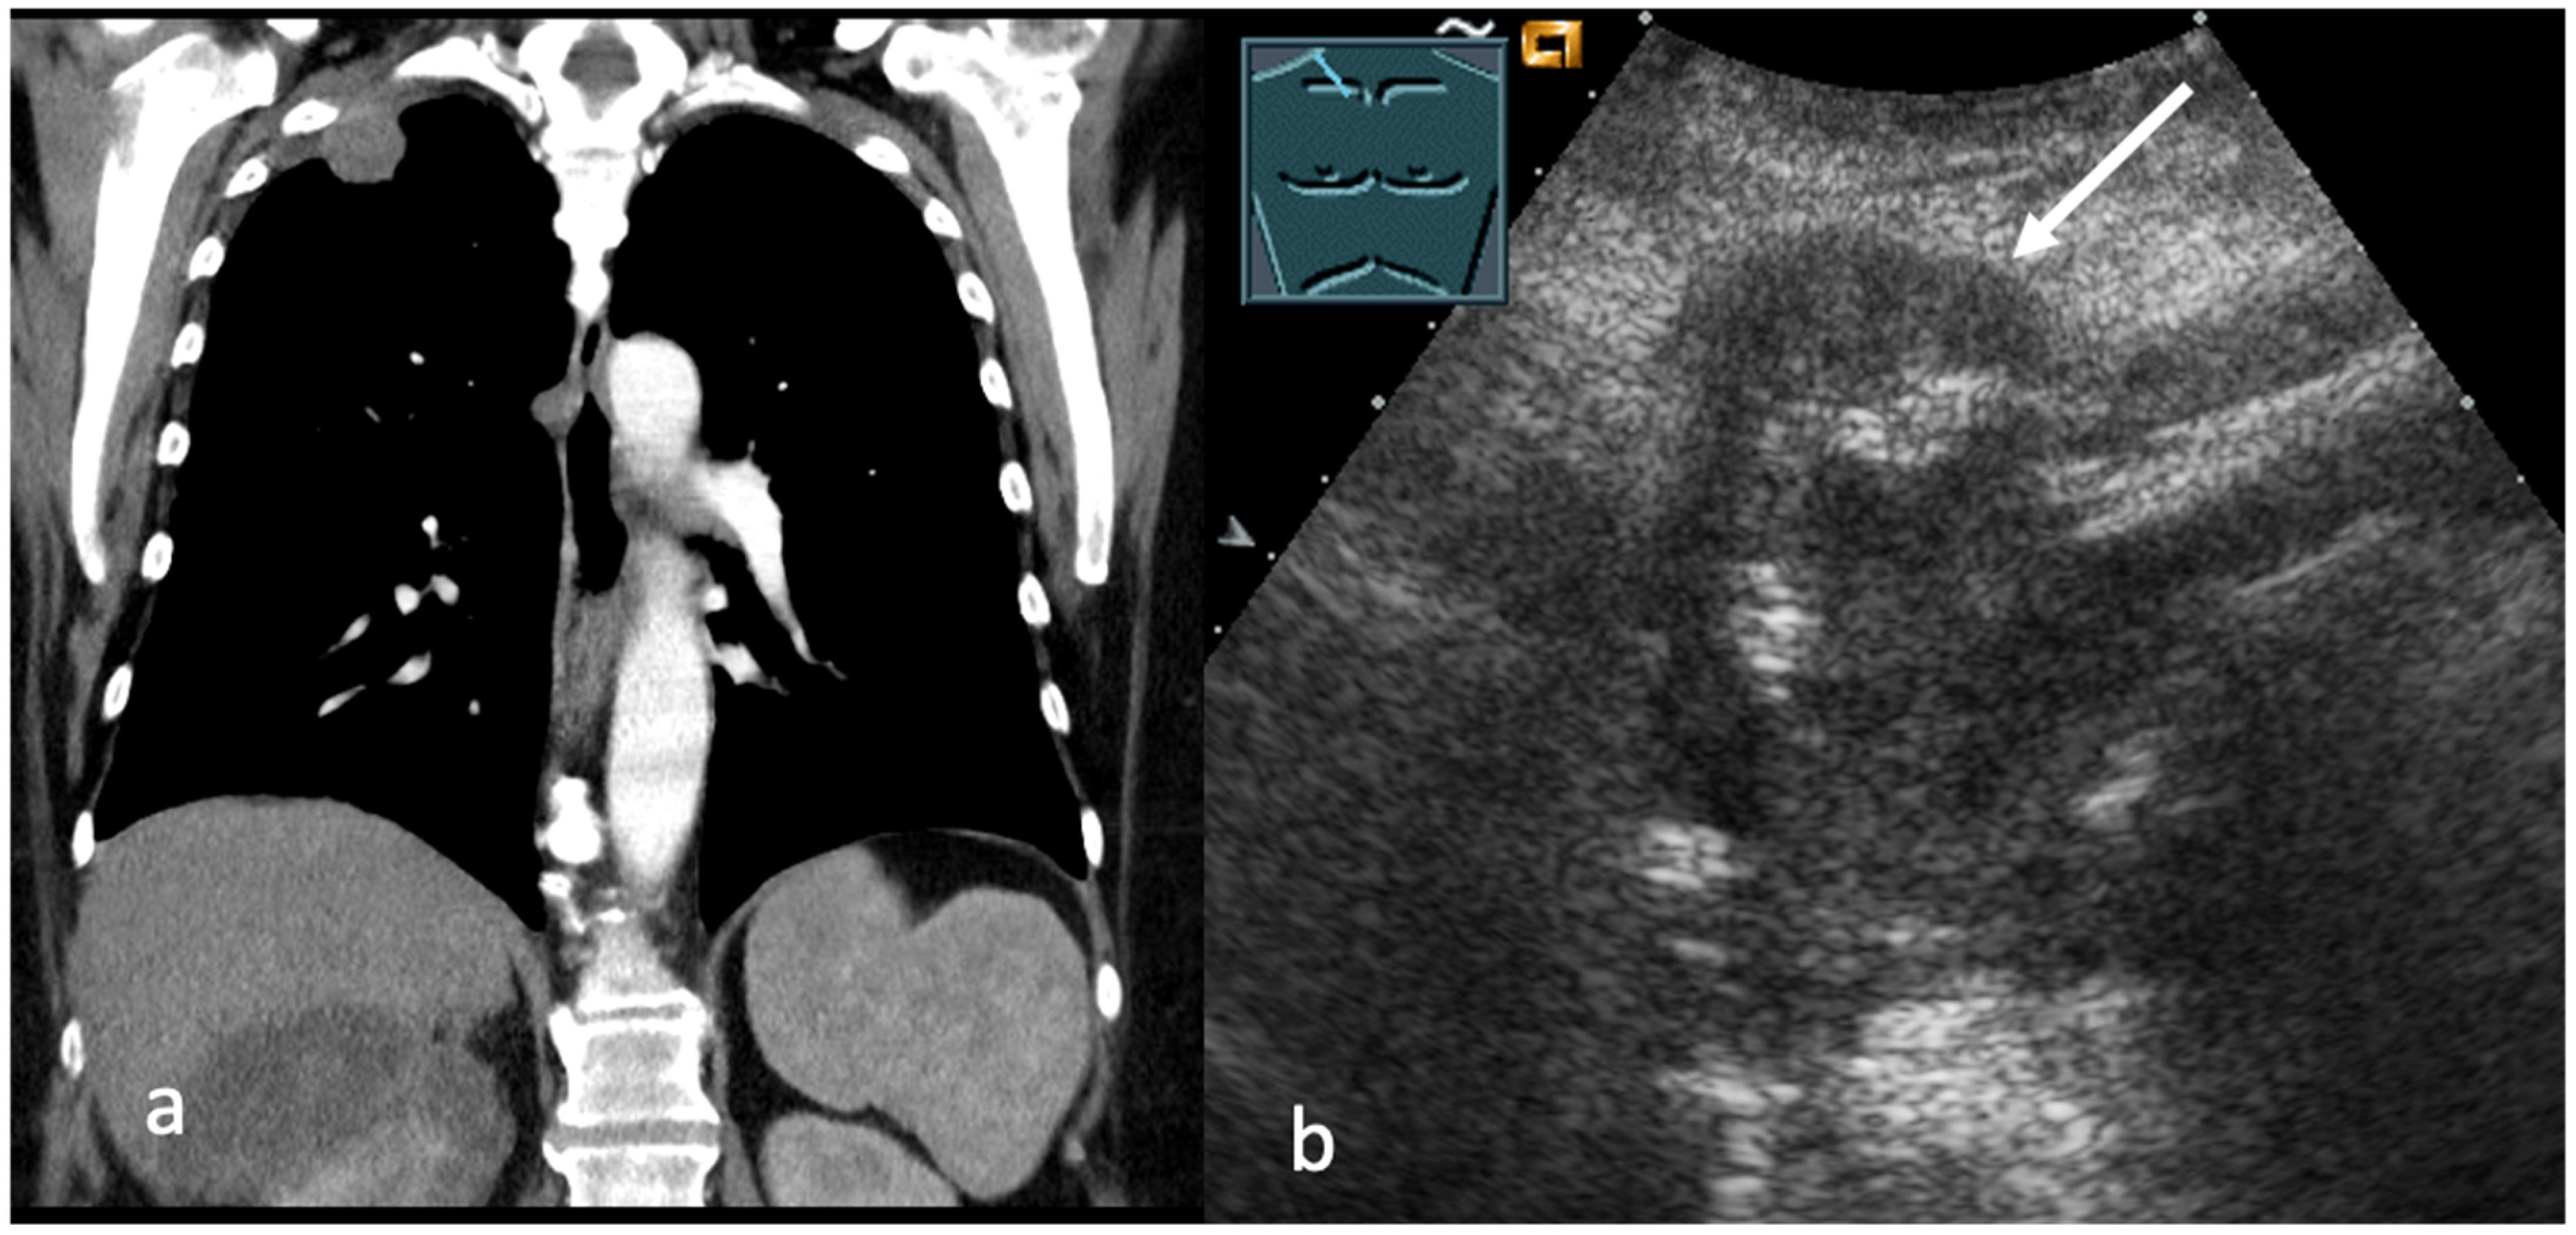

3. Transthoracic Ultrasound in the Evaluation and Characterizing of Local Tumor Size (T-Stage)